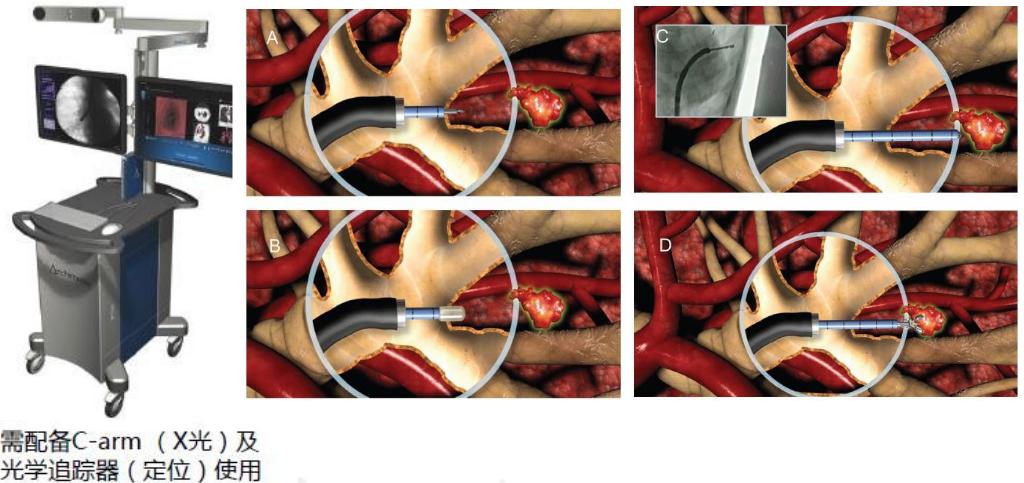

LungPro(阿基米德)全肺多模态增强现实导航诊疗系统

阿基米德也是一个很重要的系统,主要作用是有一种术式,经支气管镜引导的肺活检。

Lungpro系统可以实时和虚拟图像全程同步导航;实时C型臂X线透视,3D可视光标定位靶点并显示路径引导;虚拟多普勒检测血管,实现血管可视化。

BTPNA对PPL的诊断价值

这是一项全球的多中心研究,我们中心贡献的例数最多,总的活检诊断率是84.8%,它的特点就是通过打孔可以做那些没有气道通向的技术。